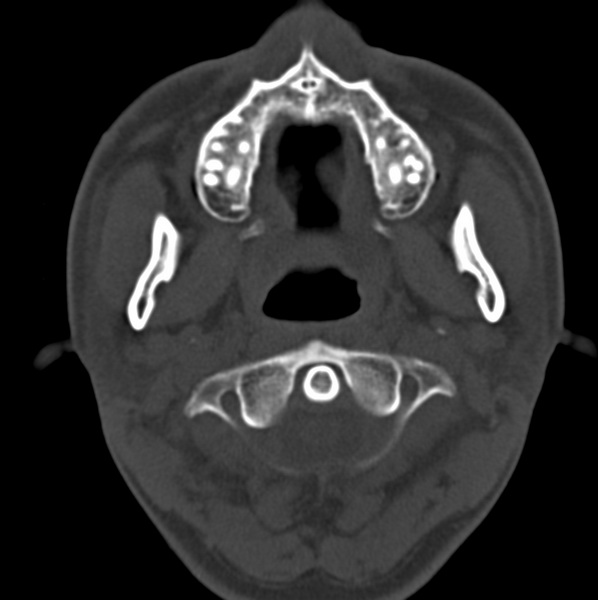

男、31、鼻咽部肿瘤放疗后请帮忙看看。

效果好,右侧破裂孔扩大,局部骨质缺损,为颅底骨质破坏。

1)鼻咽部肿瘤侵犯颅底放疗术后改变。2)左侧蝶窦炎。

咽后壁增厚,左侧咽鼓管隆突增大、咽鼓管咽口变浅,同侧咽旁间隙较窄。右侧颅底骨质破坏?为什么不在同一侧?

鼻咽部肿瘤侵犯颅底放疗术后改变.